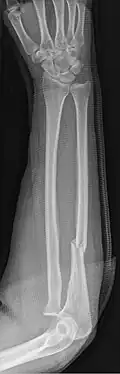

An ulna fracture is a break in the ulna bone, one of the two bones in the forearm.[2] It is often associated with a fracture of the other forearm bone, the radius.[1][3]

Fractures of the ulna can occur at different levels of the bone: near the wrist, in the middle or near the elbow.[2] The fracture may be confined to the ulna or accompanied with damage to the radius or the wrist or elbow joints.[2]

- Nightstick fracture is a fracture of the middle portion of the ulna without other fractures.[1]

- Distal ulna fractures typically occur along with distal radius fractures.[3]

- Hume fracture - a fracture of the olecranon with an associated anterior dislocation of the radial head.[6]

- Monteggia fracture - a fracture of the near to elbow end of the ulna with the dislocation of the head of the radius at the elbow joint.[2]

- Galeazzi fracture - not a fracture of the ulna but a displaced fracture of the radius accompanied by a dislocation of the ulna at the wrist, where the radius and ulna come together.[2]